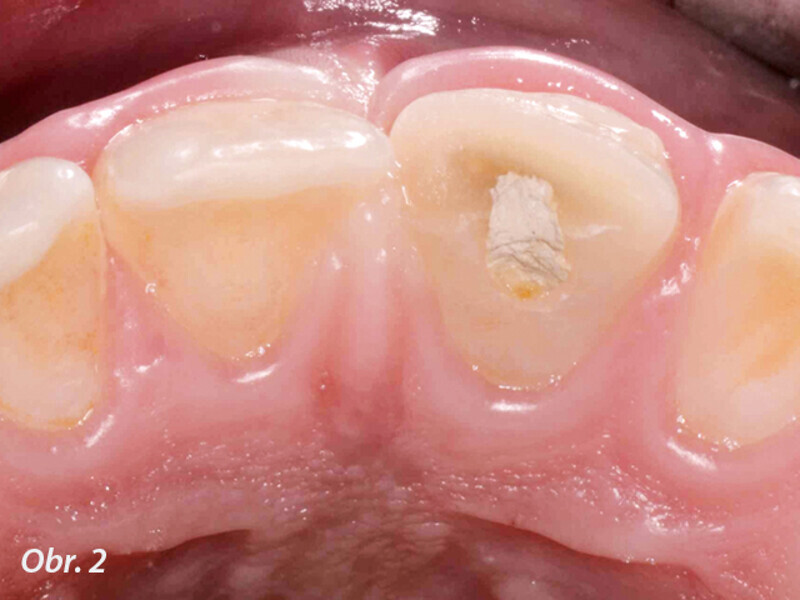

Endodontické ošetření horního středního řezáku s atypickou anatomií